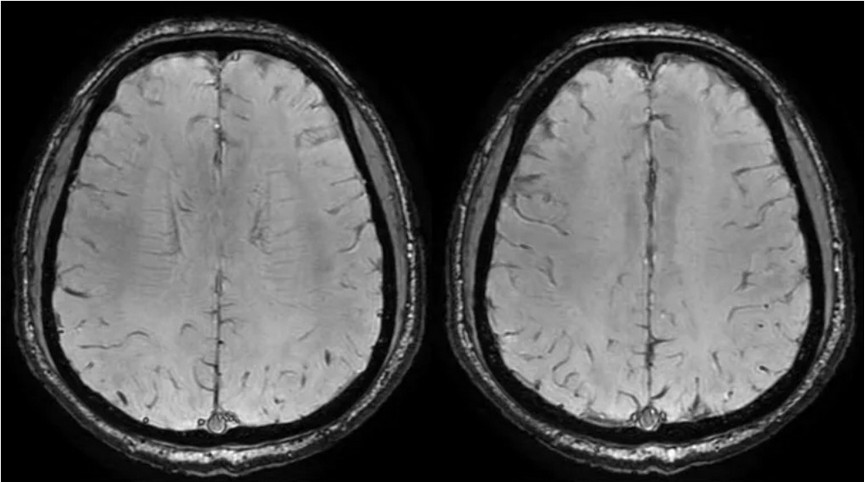

PC-MRV未见异常。

颅内静脉黑血成像,CUBE T1fs w/o +c,静脉窦未见异常。